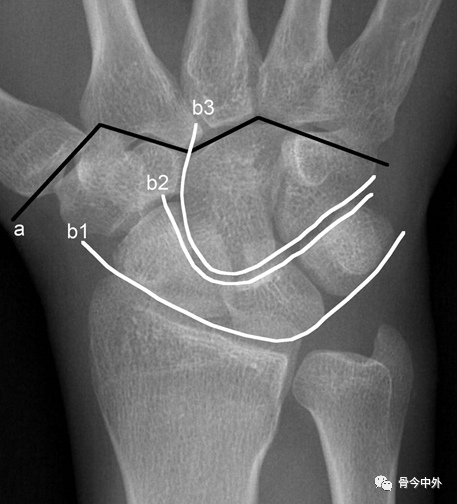

腕关节x线解剖(正侧位标准对照,常用测量方法)及读片技巧

详细的腕关节x线解剖 摄影技巧 阅片技巧 测量

腕关节x线解剖及诊断,这份图谱太实用了